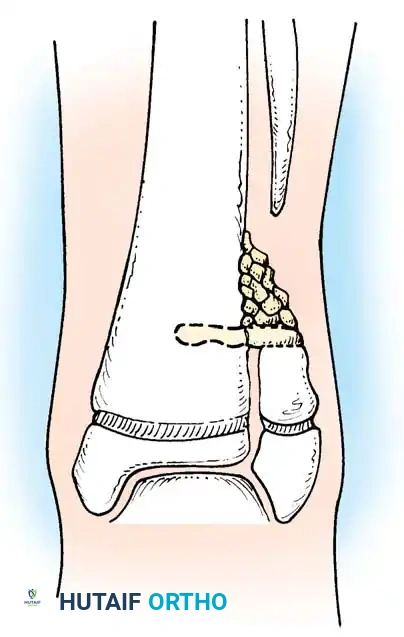

Fig. 26-53 Langenskiöld technique for creating synostosis between distal tibial and fibular metaphyses to prevent valgus deformity of ankle in congenital pseudarthrosis of fibula.

SURGICAL TECHNIQUE: Tibiofibular Synostosis (Langenskiöld)

Indications: Progressive ankle valgus in a growing child with congenital pseudarthrosis of the fibula.

Positioning: Supine with a bump under the ipsilateral hip to internally rotate the leg, bringing the lateral malleolus into clear view. A thigh tourniquet is applied.

- Surgical Approach: Make a longitudinal incision anteriorly over the distal fibula, carefully avoiding the superficial peroneal nerve.

- Fibular Resection: Divide the fibula 1 to 2 cm proximal to the level of the distal tibial physis. Excise the cone-shaped, dysplastic part of the distal fibular shaft to expose healthy bone.

- Tibial Preparation: On the lateral surface of the tibia, exactly at the level of the cut surface of the fibula and at the attachment of the interosseous membrane, create a cortical window (hole) as wide as the diameter of the fibula.

- Periosteal Stripping: Proximal to this hole, meticulously elevate and remove the periosteum and interosseous membrane from the tibia over an area of several square centimeters to provide a vascularized bed for the graft.

- Graft Harvest: From the ipsilateral iliac crest, harvest a structural corticocancellous bone graft. The graft must be the same width as the tibial hole and long enough to span from the lateral surface of the fibula deep into the spongy cancellous bone of the tibial metaphysis.

- Graft Insertion: Insert the structural graft perpendicular to the long axis of the limb. Ensure it rests securely on the cut surface of the fibula and extends deeply into the slot created in the tibial cortex.

- Cancellous Packing: Pack additional spongy autogenous iliac bone tightly into the angle between the proximal surface of the structural graft and the lateral surface of the tibia to maximize osteogenesis.

- Closure and Immobilization: Close the wound in layers. Apply a well-padded, long-leg cast from below the knee to the base of the toes, ensuring the ankle is held in a neutral position.